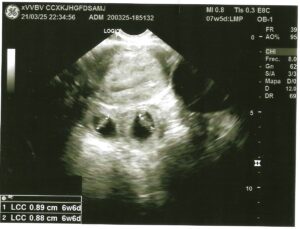

Laboratory testing showed a serum β-subunit of human chorionic gonadotropin (β-hCG) level of 56,172 mIU/mL. All other laboratory parameters were within normal limits. Transvaginal ultrasound demonstrated an empty uterus with an endometrial thickness of 9 mm. A 40 × 38 mm anechoic image, consistent with a corpus luteum, was identified in the left ovary, while the right ovary had a normal ultrasound appearance. Adjacent to the right ovary, two gestational sacs were visualized, each containing an embryo with a crown–rump length of 8.9 mm and 8.8 mm, corresponding to 6 weeks and 6 days of gestation. Cardiac activity was detected in both embryos (Figure 1).